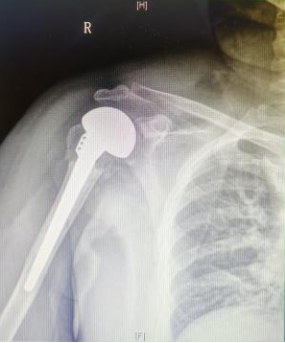

术后康复:悉心照料,成效显著

术后,患者病情稳定,拍片显示假体位置良好。在石颖、王红伟护士长带领的护理团队精心护理下,患者顺利康复并出院。患者及家属对手术效果非常满意,对骨科医护团队的专业素养与敬业精神给予高度评价。

术后复查X线片